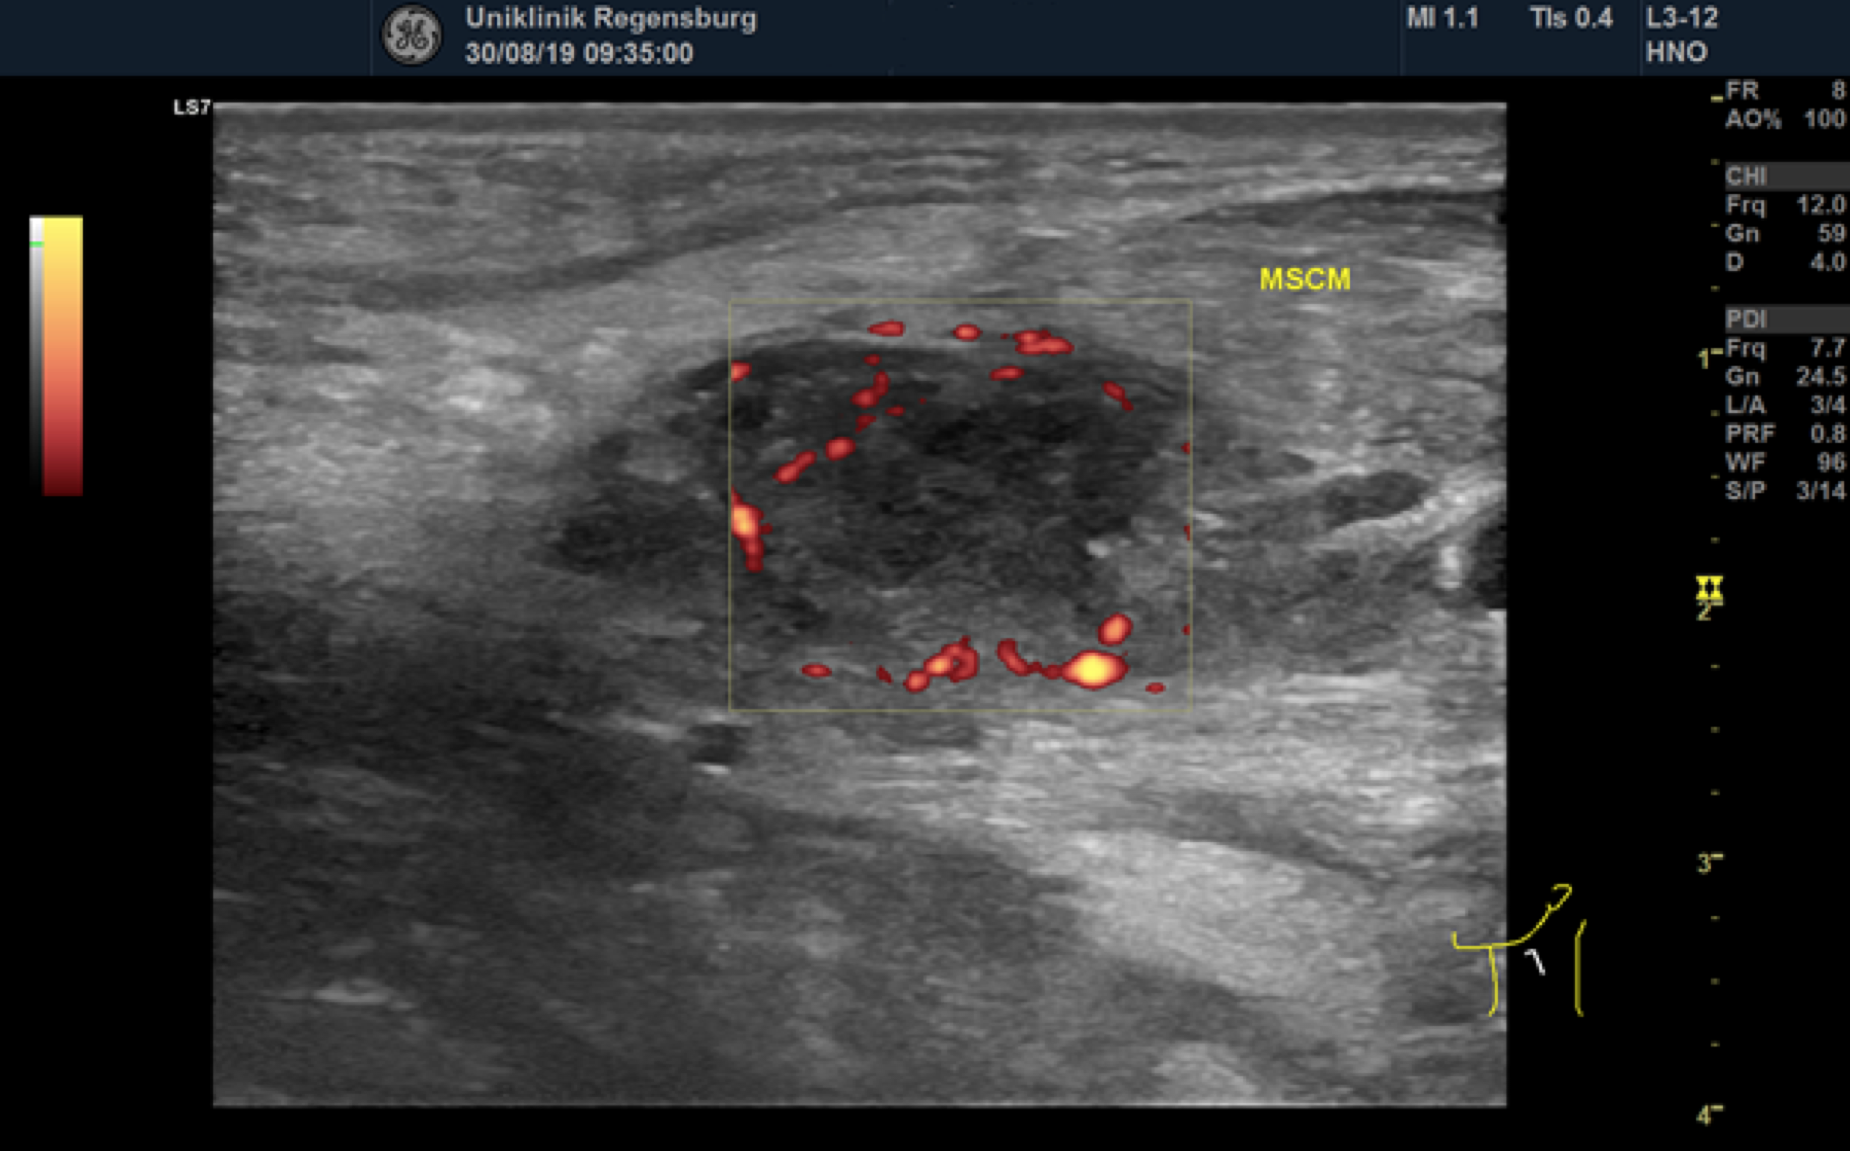

Preoperative ultrasonographic findings showed an oval hypoechoic inhomogeneous mass, approximately 4 x 3 x 1.5 cm in levels III to IV of the left side of the neck below the sternocleidomastoid muscle. (Fig. 1) The mass was partly indistinct to the adjacent tissue and demonstrated peripheral perfusion with no central vascularity. (Fig. 2) The surrounding soft tissues appeared oedematous and thickened. (Fig. 1 – 2)